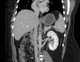

Circumaortic inferior vena cava

The renal veins are veins that drain the kidney. They connect the kidney to the inferior vena cava. [Source: Wikipedia ]